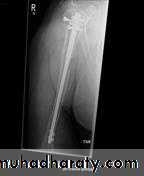

د.محمد الموسوي 12-10-2015Fracture shaft of humerus:

Traumatic & pathological3-5% of all fractures

Fracture location: proximal, middle or distal third.

Fracture pattern: spiral, transverse, comminuted or oblique.